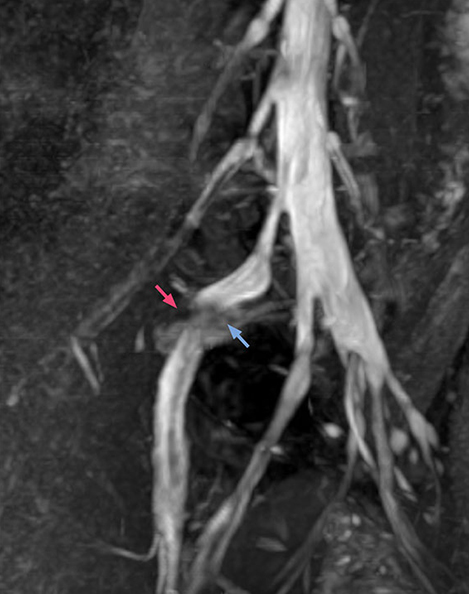

“In such case, we would then browse through axial T2-weighted MR images slice by slice and mentally reconstruct the actual situation based on both radiculography and MRI. Fortunately, NerveVIEW can now very well show nerve courses and presence of nerve compression or edema in one single image series.” “We have often seen NerveVIEW directly depict details of the nerve compression that were not observed by radiculography. Therefore, we think that with NerveVIEW we can reduce the number of invasive examinations, especially for some patients with lumbar plexus symptoms.”

“Before NerveVIEW, diagnosis by MRI alone was sometimes difficult, unless there was a strong suspicion based on clinical symptoms,” says Shoji Yabuki, MD, DMSc, Orthopedic surgeon at Fukushima Medical University School of Medicine. “This is why we routinely perform selective lumbosacral radiculography (nerve root block) and x-ray in such cases. However, radiculography can only depict nerves as far as the contrast agent reaches. When a nerve is distorted by compression, the contrast agent will not pass through this compressed area, preventing us from evaluating the full nerve compression.”

The key concept in MR neurography, Dr. Yabuki stresses, is the ability to directly visualize spinal nerves, versus inferring the presence of pathology indirectly. “Before NerveVIEW, we estimated compression of the nerve by looking for the presence or absence of fat signal on other MR images,” he says.

“For example, in sagittal images, when the presence of fat is observed in the intervertebral foramen, it suggests that there is a margin around the nerve. Similarly, the absence of fat indicates that the nerve is being compressed. So, we used to deduce nerve compression indirectly. With NerveVIEW, however, we can observe the condition of the nerves directly, regardless of the presence or absence of fat. We always prefer such direct observation of anatomy over having to make an inference about it.”